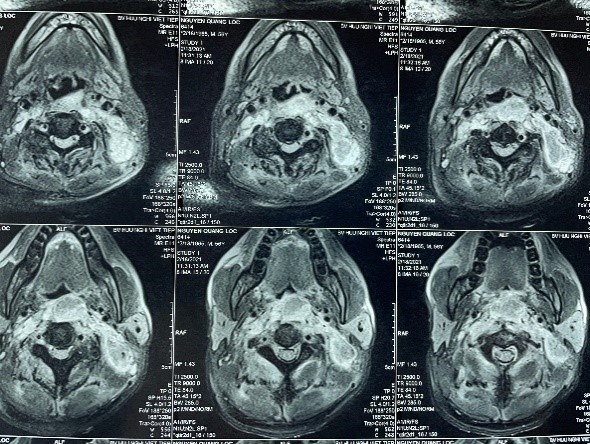

Từ phim chụp cộng hưởng từ, các bác sĩ xác định có 2 ổ áp-xe phía trước cột sống và cạnh cổ trái. Nam bệnh nhân được chỉ định phẫu thuật nhằm dẫn lưu, phá ổ áp-xe. Kết quả vi sinh cho thấy ông bị nhiễm khuẩn Staphylococcus Aureus (tụ cầu vàng).

Trên phim chụp, ổ áp-xe thấy rõ ở trước cột sống, có chèn ép vào khí quản cổ. Ảnh: BVCC.